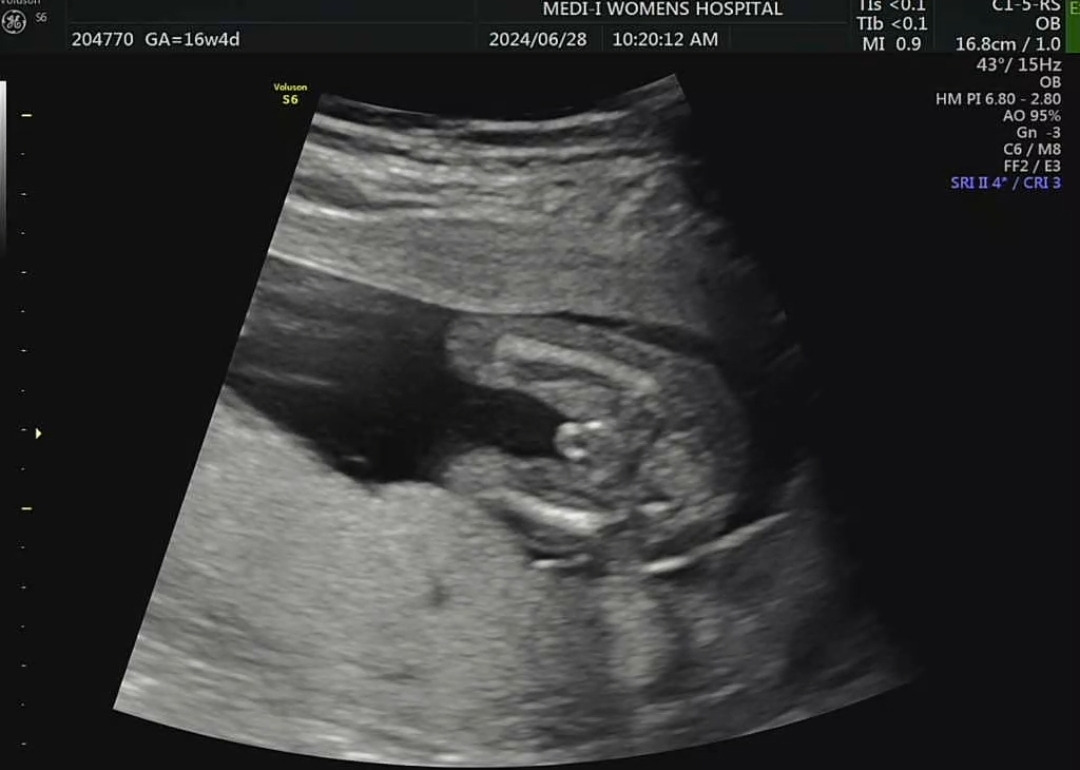

밑에서 본 아기 초음파. 두 다리 사이에 뭔가가 보인다.

초음파 상으로 '고추'로 추정되는 무언가를 보긴 봤다. 의사 선생님께서 "여기 보이는 것 같죠?" 하시며 아기 다리 사이에 살짝 튀어나온 곳을 가리키셨다. 그러면서 덧붙이시기를 "아들일 가능성이 지금은 훨씬 높은 것 같네요. 하지만 확실하지 않아서 20주 정밀초음파를 기다려봅시다"하셨다.